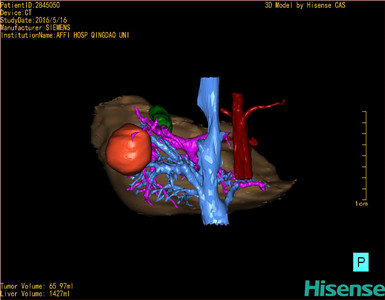

通过调节窗宽窗位调整CT序号,对肿瘤,肝实质,胆囊,下腔静脉,肿瘤,肝动脉、门静脉及肝静脉等进行三维重建;系统自动计算肿瘤体积和肝脏体积。

模拟手术操作,自动计算切除肿瘤体积。肝脏体积为1427ml,肿瘤体积为65.97ml,肿瘤体积为肝脏体积的4.6%,通过比对40-50岁正常肝脏体积为1368.38±279.24ml,通过术前模拟手术,精准判断切除后剩余肝脏体积能耐受,避免肝衰竭发生。

术前手术方案的规划。

术前三维重建:

重建图片